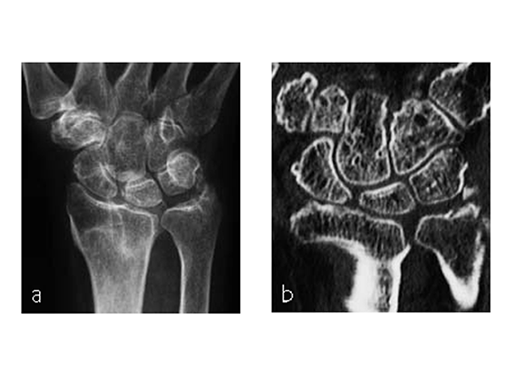

A 69-year-old female patient had suffered a right distal radius fracture one year earlier, and received conservative management. Symptoms included pain and impaired function about the wrist and forearm, with decreased forearm rotation. Painful DRUJ (DASH: 34, PWRE: 29).

The amount of correction required was 2.5 mm. The preoperative x-ray showed positive ulna variance.